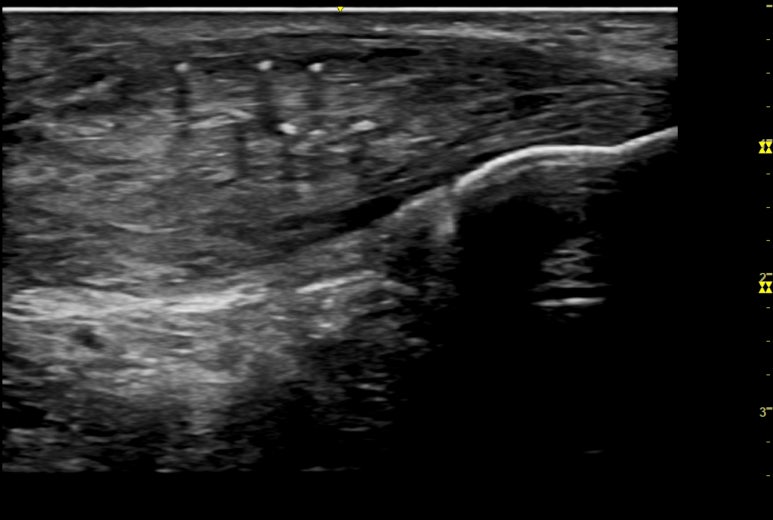

두번째 환자분은

경기도 일산에서 오신 분인데요.

표준 초음파 영상과 달리

이 환자분 영상의

친 곳에

하얀 돌 표면이 보입니다.

침을 놓을 때

힘줄 안에 석회를

세게 찌르면

칼슘이 흡수되면서

염증을 일으키게 됩니다.

가뜩이나 염증으로 아픈데

침 맞고 더 아프실 수 있거든요.

안전하고 정확한 침 치료를 위해

반드시 초음파로 체크해봐야 합니다.